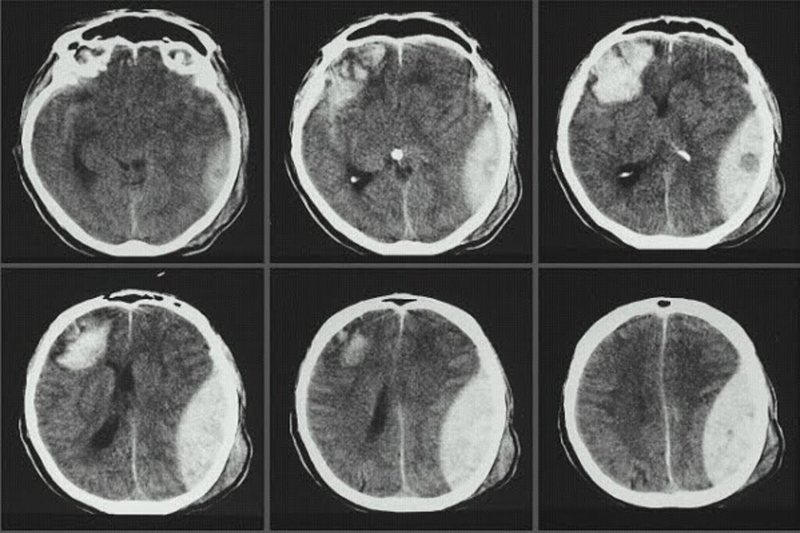

• Sự thay đổi màu sắc của dịch não tủy: Bình thường dịch não tủy có màu trắng trong nhưng khi bị bệnh, màu sắc có thể thay đổi theo từng bệnh lý. Những bệnh nhân bị chấn thương sọ não, vỡ dị dạng mạch máu, xuất huyết não, viêm màng não tối cấp... dịch não tủy thường có màu đỏ. Đối với những trường hợp xuất huyết lâu ngày mới tiến hành chọc dịch hoặc lao màng não thì dịch não tủy thường màu vàng. Tình trạng dịch não tủy đục thường là viêm màng não mủ.

Tìm hiểu nguyên nhân và biểu hiện thường gặp của người mắc hội chứng màng não 3 Chấn thương sọ não làm thay đổi màu sắc dịch não tủy